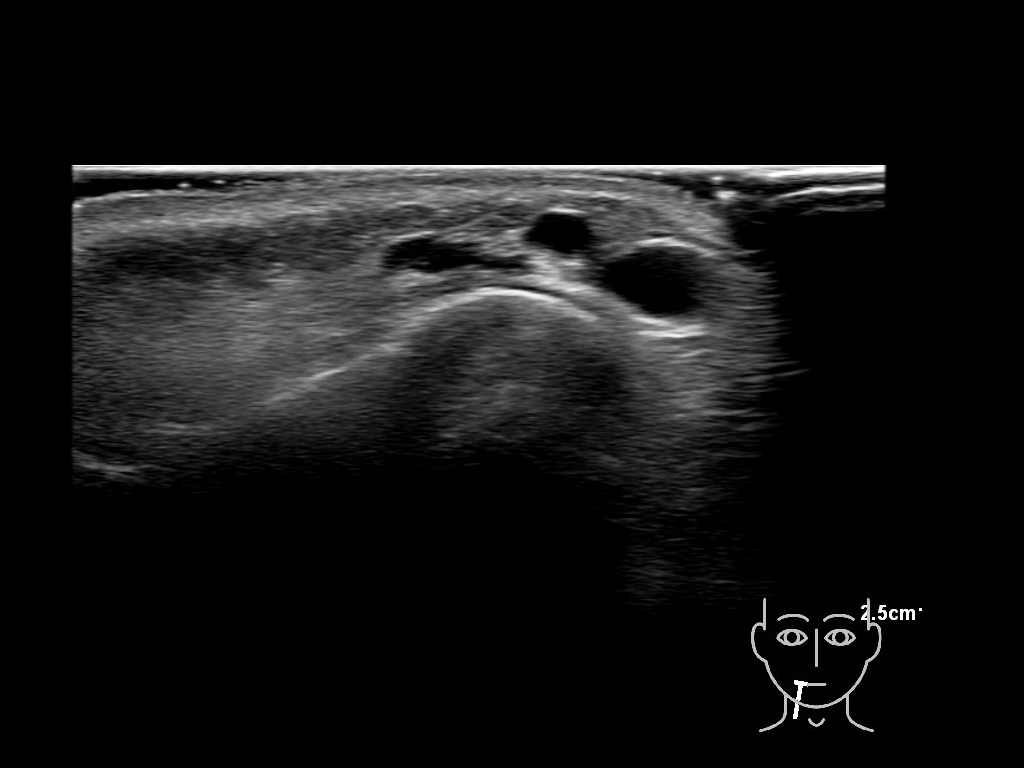

Filler deposits may end up unintentionally in the SMAS or fascial layers of the skin. Very often this will not lead to adverse events, however, adverse events ( nodules, migration / redistribution impaired muscle movement and smiling and malar edema) are are often related to filler ending up in the SMAS or fascia.

Study the first image to recognize the different layers. If you are sure about the layers, swipe to the second image to view the answer (if applicable).